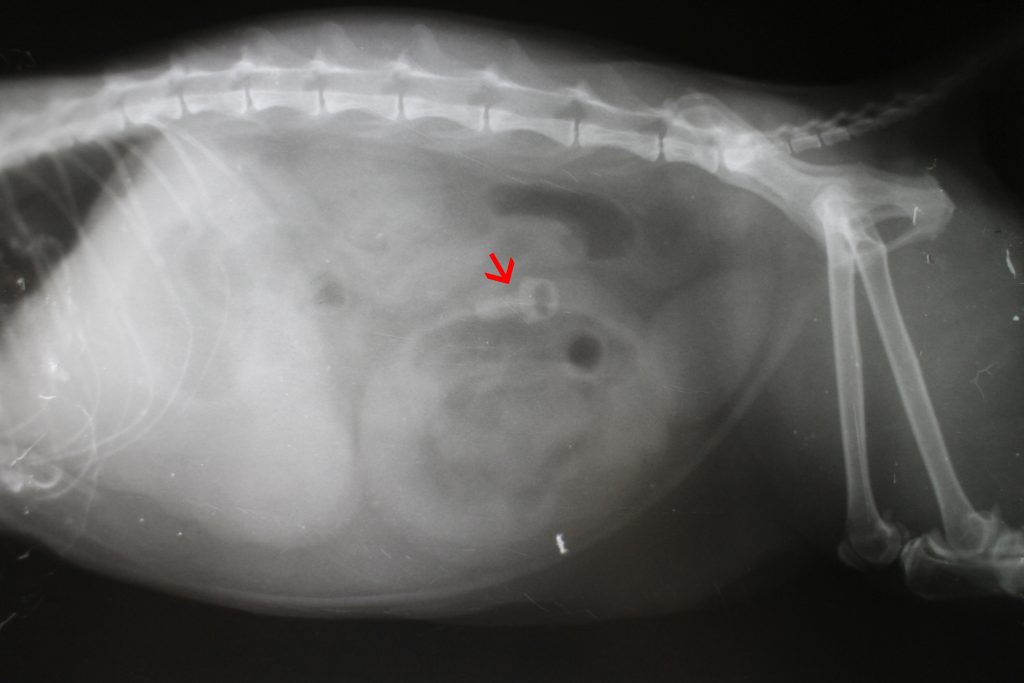

X-ray picture of foreign body in abdominal cavity by cat

1枚目のレントゲン写真は(赤矢印)、異物を指しています。このようなケースは一発で異物の存在を明らかにしてくれますが、まずレントゲン検査で写ってくれればの話です。経験上、金属など以外の異物でここまでクリアにはまず写りません。私たち獣医師は、異物自体だけでなく、腸のガスの溜まり具合なども参考にレントゲン検査で見ています。